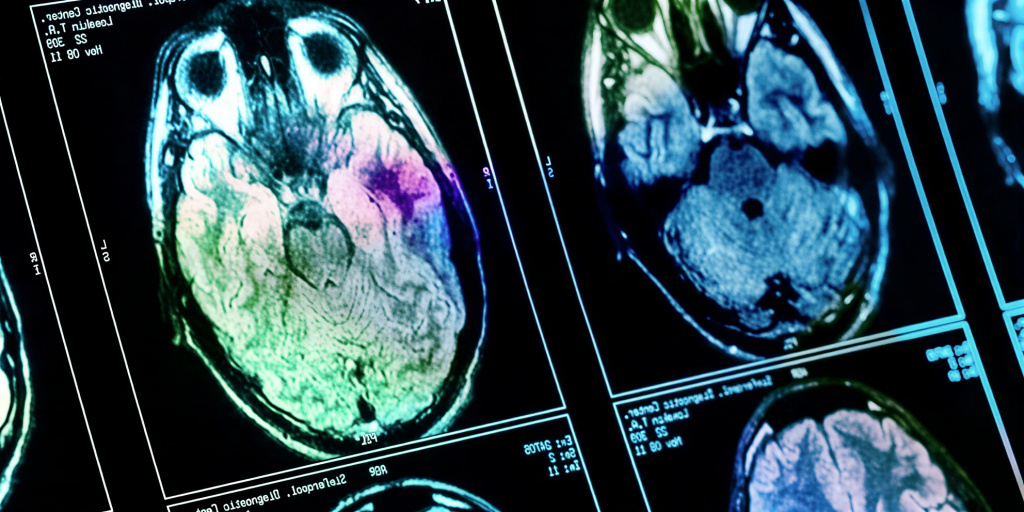

В рамках научной работы, опубликованной в Европейском журнале неврологии, команда под руководством Кёнджуна Пака проанализировала данные позитронно-эмиссионной томографии 233 здоровых мужчин. Средний возраст участников составлял 43 года. Все они прошли обследование в медицинском центре в 2013 году. Исследователи изучили снимки мозга, а также информацию о годовом доходе семьи, уровне образования, показателях стресса, тревожности и депрессии.

Анализ данных выявил четкую закономерность. Более высокий семейный доход был связан с повышенным метаболизмом глюкозы (показателем нейронной активности) в нескольких ключевых областях мозга. К ним относятся хвостатое ядро, скорлупа, передняя поясная кора, гиппокамп и миндалевидное тело.

Эти структуры играют центральную роль в системе вознаграждения, обработке эмоций и регуляции реакции на стресс. Проще говоря, у более обеспеченных мужчин наблюдалась более активная работа нейронных сетей, отвечающих за чувство удовлетворения и управление стрессом.